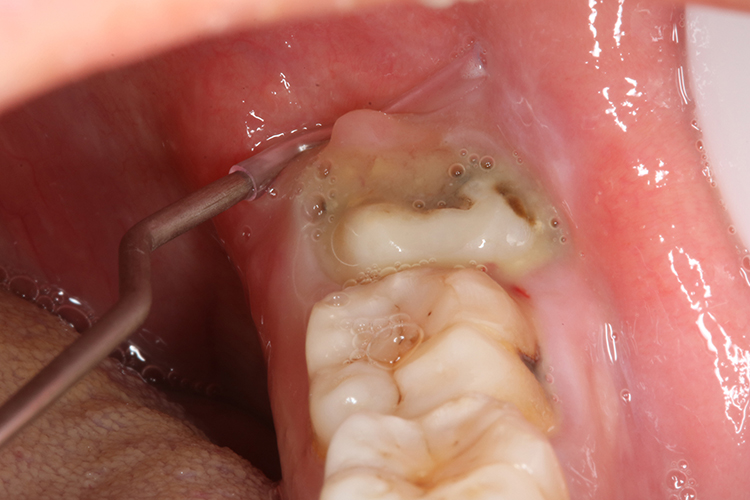

智齿冠周炎

牙齿周围红肿疼痛,有时龈袋内有脓性分泌物溢出,造成张口困难,颌下淋巴结肿大压痛,这时如不及时治疗,炎症将继续发展,引起面部明显肿胀、全身不适、发烧、食欲减退、大便秘结等症状。

根据临床表现及体征,较易做出诊断。对牙冠完全被龈瓣覆盖的阻生智齿的检查,可用探针顺龈袋仔细探查。另外,拍x线牙片有助于了解阻生智齿的位置、牙根情况、牙周状态以及邻牙的情况。对张口受限无法拍牙片者可拍全口曲面断层片。

如果智齿位置正常,只是牙面上有牙龈覆盖,可在消炎后切除牙冠上覆盖的龈瓣,等待智齿自行萌出,不需要拔除。如果发现智齿是倾斜的,不能顺利萌出,就应当尽早拔除。如果已经发生智齿冠周炎,应用磺胺类或抗菌素等药物积极治疗,防止炎症扩散。如果已形成脓肿,应尽早切开排脓。